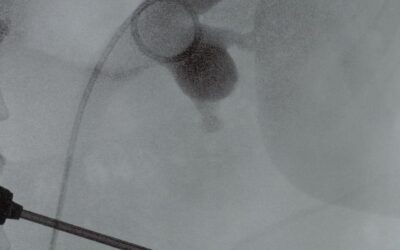

L’adénome de la prostate

et sa prise en charge par énucléation prostatique au laser (HoLEP)